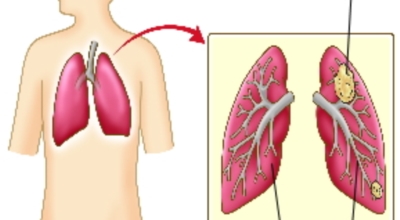

폐암에 관해서

폐에 발생된 악성 종양을 말하며 오랜 기간 흡연해온 남성들에서 발병률이 높고 요즘 들어 가지가지 환경적인 요인의 영향과 간접흡연으로 흡연하지 않는 여성에서도 많이 발생하고 있답니다. 증상을 느껴 병원을 찾았을 때는 수술하기 늦은 경우가 많아 사망 확률이 매우 높은 암입니다. 폐 자체에서 생기거나 다른 장기에서 발생된 암이 폐로 전이되어 나타나기도 하고 특별한 초기 증상이 없는 경우가 많으며 암이 진행된 후에도 일반적인 감기 증상인 기침과 가래 외의 특이 증상이 나타나지않아 증상만으로는 진단이 쉽지 않아요.